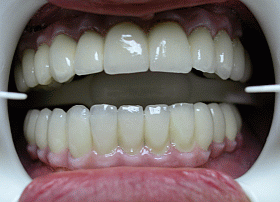

This picture shows the final result – 2 full dental bridges screwed onto implants – completing full mouth restoration with All-on-6 & All-on-4 dental implant systems.

To provide natural look to final restorations, outer bridge framework was made of pink porcelain (to imitate natural gum), which also allows for the crowns to be made to the proportion and look of natural teeth.